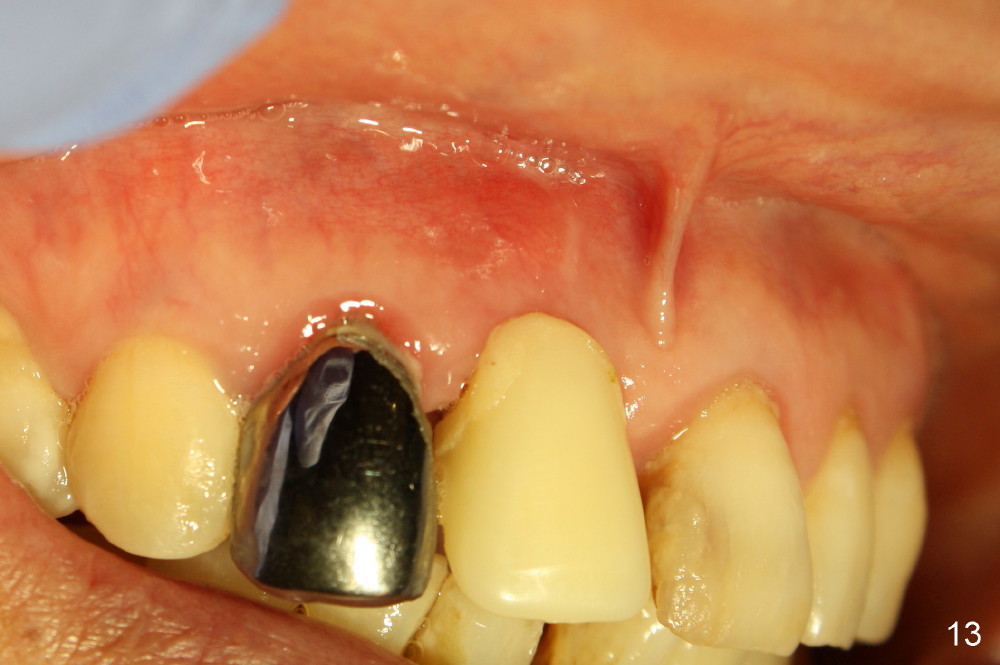

The patient returns for follow up 8 days postop and the labial margin of the provisional looks long. The metal crown is changed to a provisional at the visit. Eight days later, the provisional at the site of #8 is removed for labial margin trimming; the labial gingiva heals (Fig.14 *). The labial plate remains slightly convex (Fig.15). The labial margin of the provisional at the site of #8 is at the same level of that of #9.

Four-month follow up shows that bone graft from the tuberosity appears to have healed with the implant microthreads (Fig.17 *); there is a diastema between #8 and 9 (arrowheads). Before removal of the provisionals of #7 and 8 for final impression, new composite is added to the mesial surface of #9 as the first step of closure of the diastema (Fig.18 <).